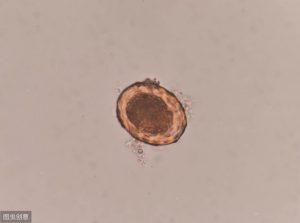

显微镜下的蛔虫卵,这个是肉眼什么也看不到的蛔虫